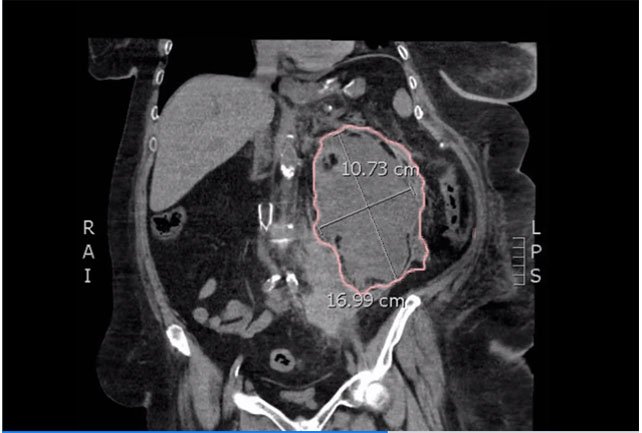

Bedside ultrasound was performed and demonstrated a hypoechoic area within the left kidney (images not shown). The non-contrast computed tomography (CT) of the abdomen and pelvis shows a significantly enlarged left kidney and a region of high-attenuation encapsulating the left kidney, concerning for acute hemorrhage.